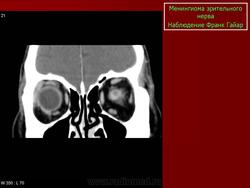

КТ-семиотика

На КТ срезах без контрастного усиления менингиома зрительного нерва выглядит изоденсной. Типично наличие линейных или точечных обызвествлений. Симптом «трамвайных рельс» отражает накопление КВ по сторонам гиподенсного зрительного нерва или наличие обызвествлений в структуре опухоли. Как правило, наиболее дистальная часть зрительного нерва, в месте его вхождения в глазное яблоко, не содержит обызвествлений.

При исследовании необходимо определить расположение бляшковидной менингиомы относительно бугорка турецкого седла и пластинки клиновидной кости, так как данный тип опухоли может распространяться интракраниально через канал зрительного нерва. КТ не позволяет адекватно визуализировать интракраниальное распространение опухоли, которое может привести к развитию двусторонней слепоты.